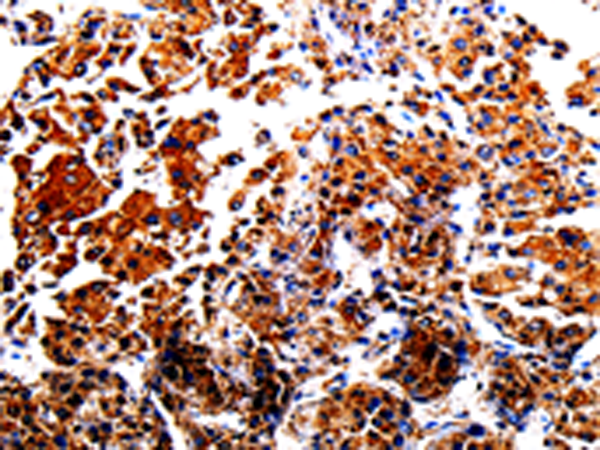

分类: 科研抗体货号: P06989别名: CPP32; SCA-1; CPP32B应用: WB,IHC反应种属: Human, Mouse, Rat